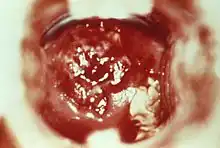

-

HSV cervicitis -

Severe cervicitis caused by schistosomiasis